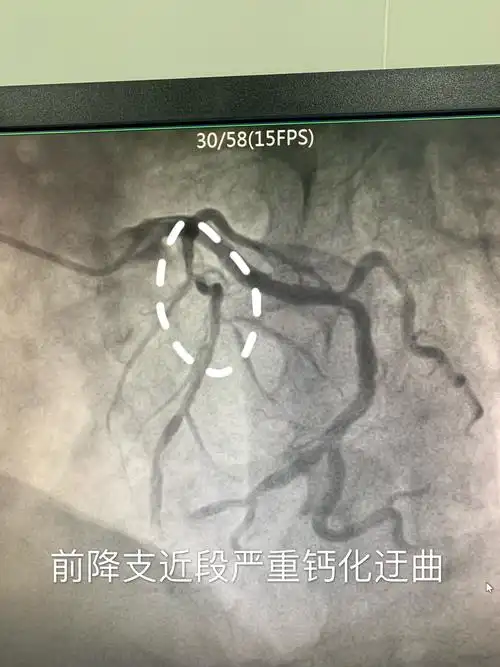

红色箭头处为左前降支堵塞近80%.医院 供图

完善各项术前准备造影结束,冠脉造影显示前降支近段重度狭窄伴严重

前降支近端狭窄

溆浦县人民医院成功独立完成一例左前降支90%狭窄的患者经皮冠状动脉

前降支远段90%狭窄